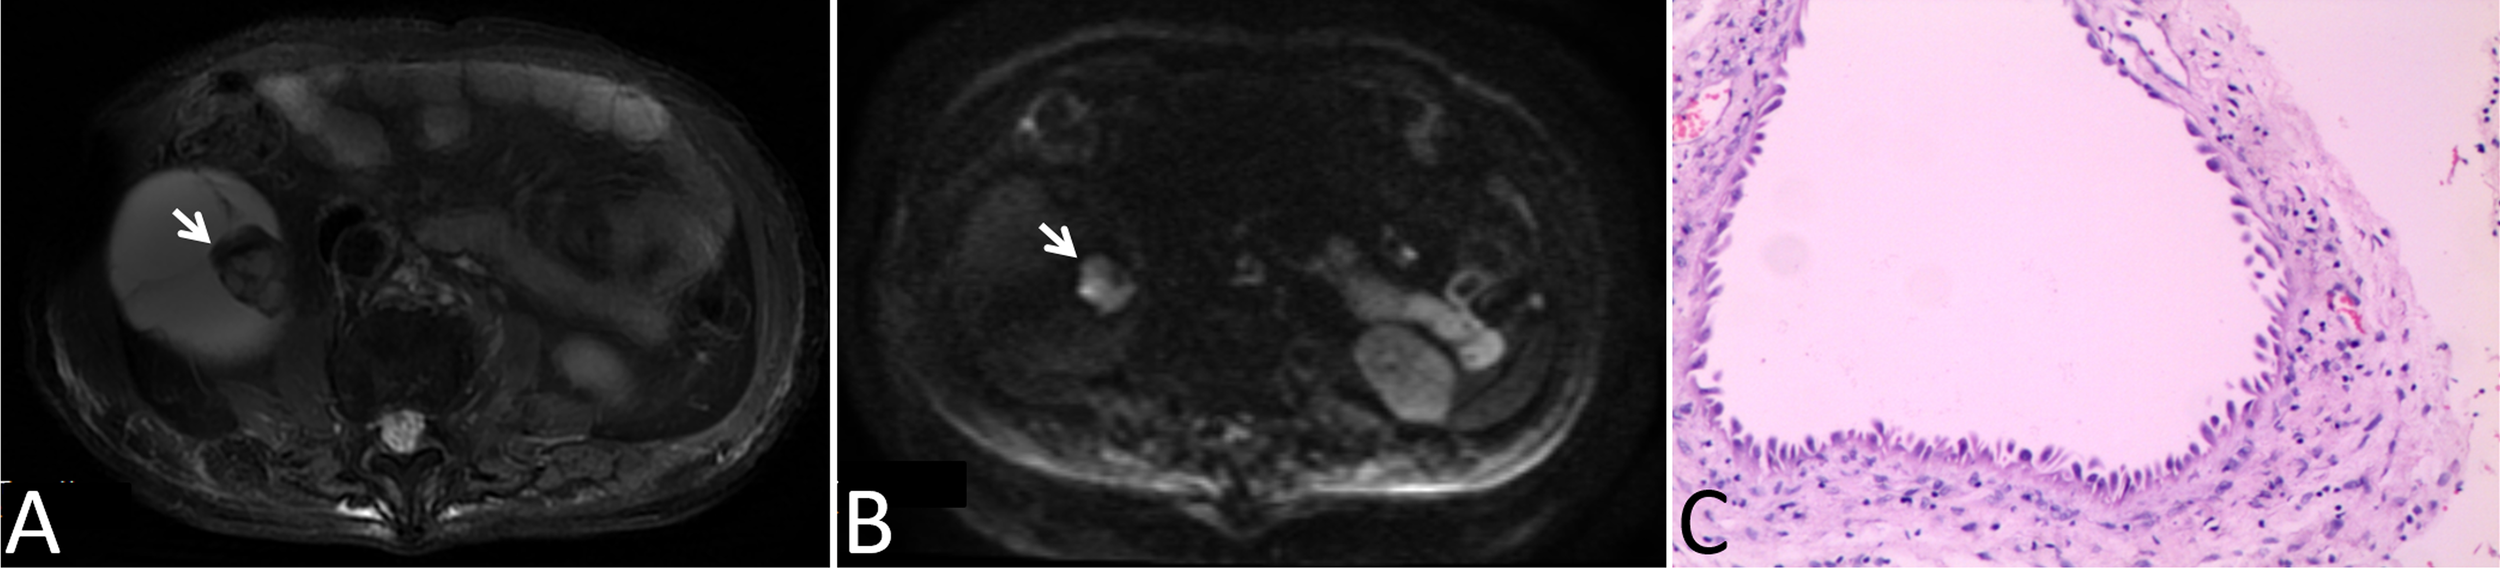

In our cohort, 87 lesions had both CT and routine MRI images, and MRI demonstrated more septa than did CT in 12 of 87 (13.8%) lesions (Figure 2). In one lesion, the cystic mass was classified as measurable enhancement of the wall on the enhanced CT because of the wall obscured by the high density calcification. Since calcification would not be depicted on the MRI, this suspected case of “pseudoenhancement” on CT has no measurable enhancement of the wall on enhanced MRI (Figure 3). Solid components of 13 cystic masses showed high signal intensity on DWI, all of which were malignant lesions (Figure 4).

Figure 4

Images in a 78-year-old man with a cystic mass in the right kidney. (A) Axial T2-weighted MR image shown mural nodular soft tissue (arrow), (B) Axial DWI (b = 1000 s/mm2) image shown remarkably high signal intensity of the wall nodule (arrow), (C) This lesion was surgically removed and determined to be a multilocular cystic renal neoplasm of low malignant potential.